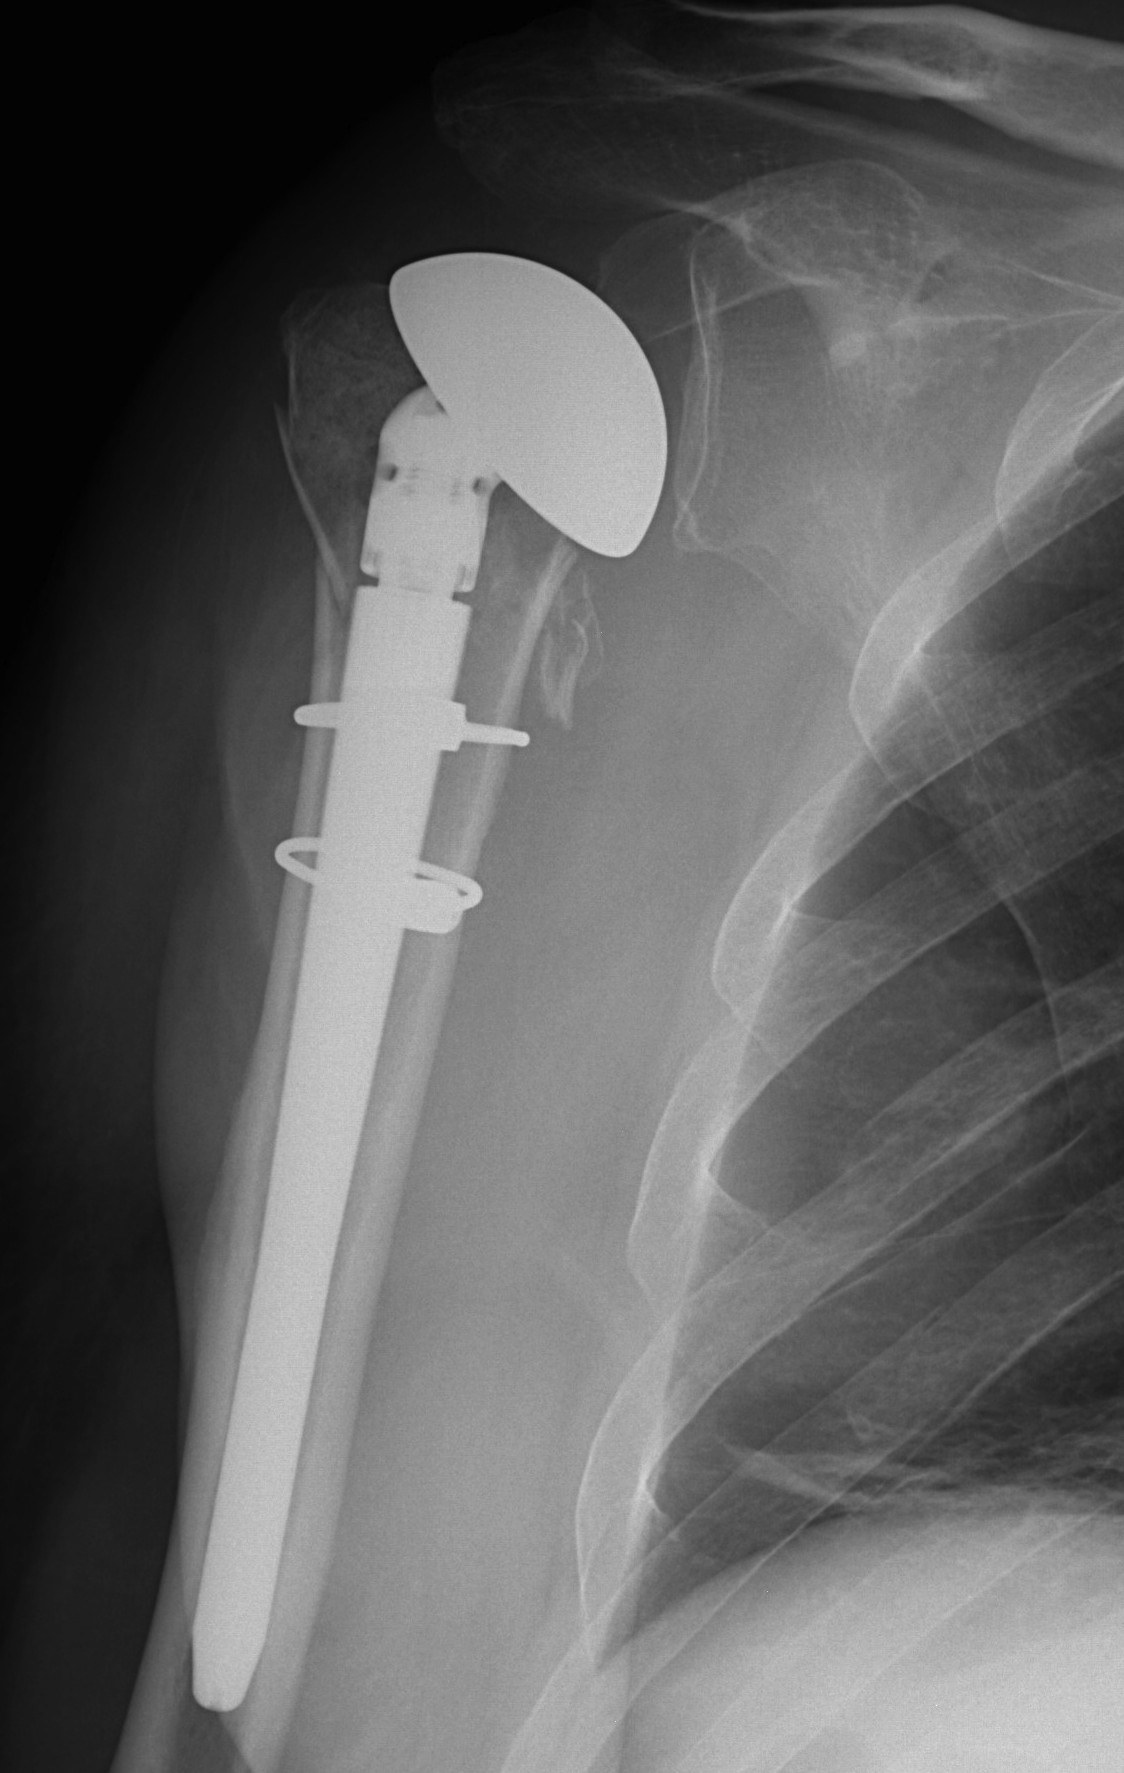

proximal humerus fracture Background ORIF with locking plate Arthroplasty Greater tuberosity fractures Lesser tuberosity fractures / avulsions Book traversal links for Proximal humerus fractures ‹ Pectoralis Major Tears Up Background ›